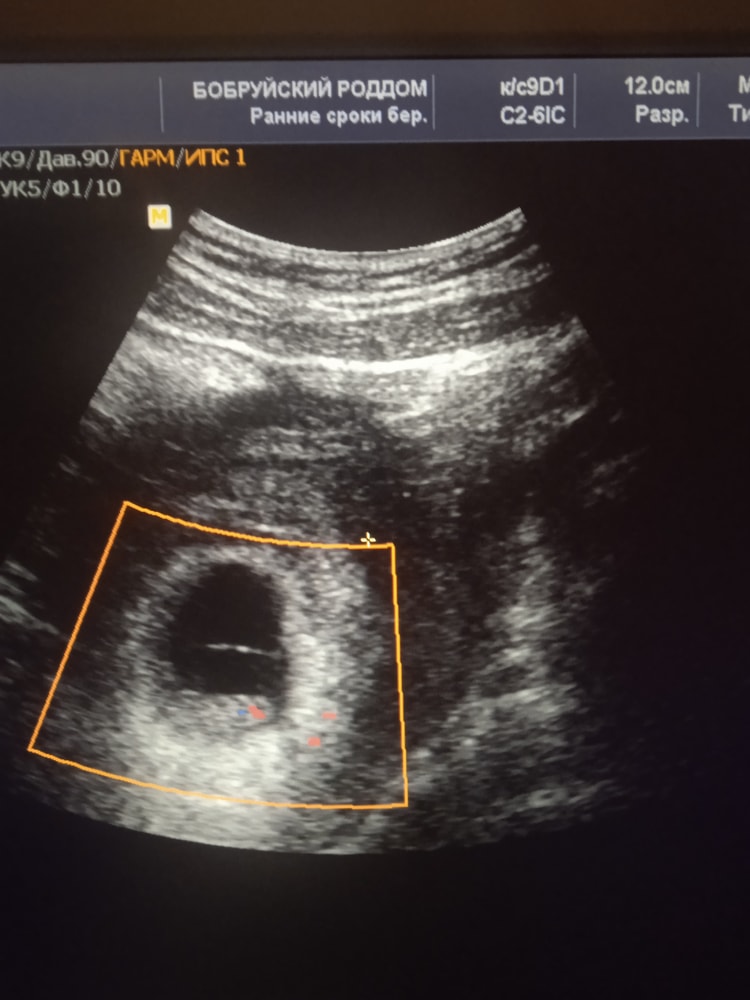

9 недель и 5 дней)) Изображение